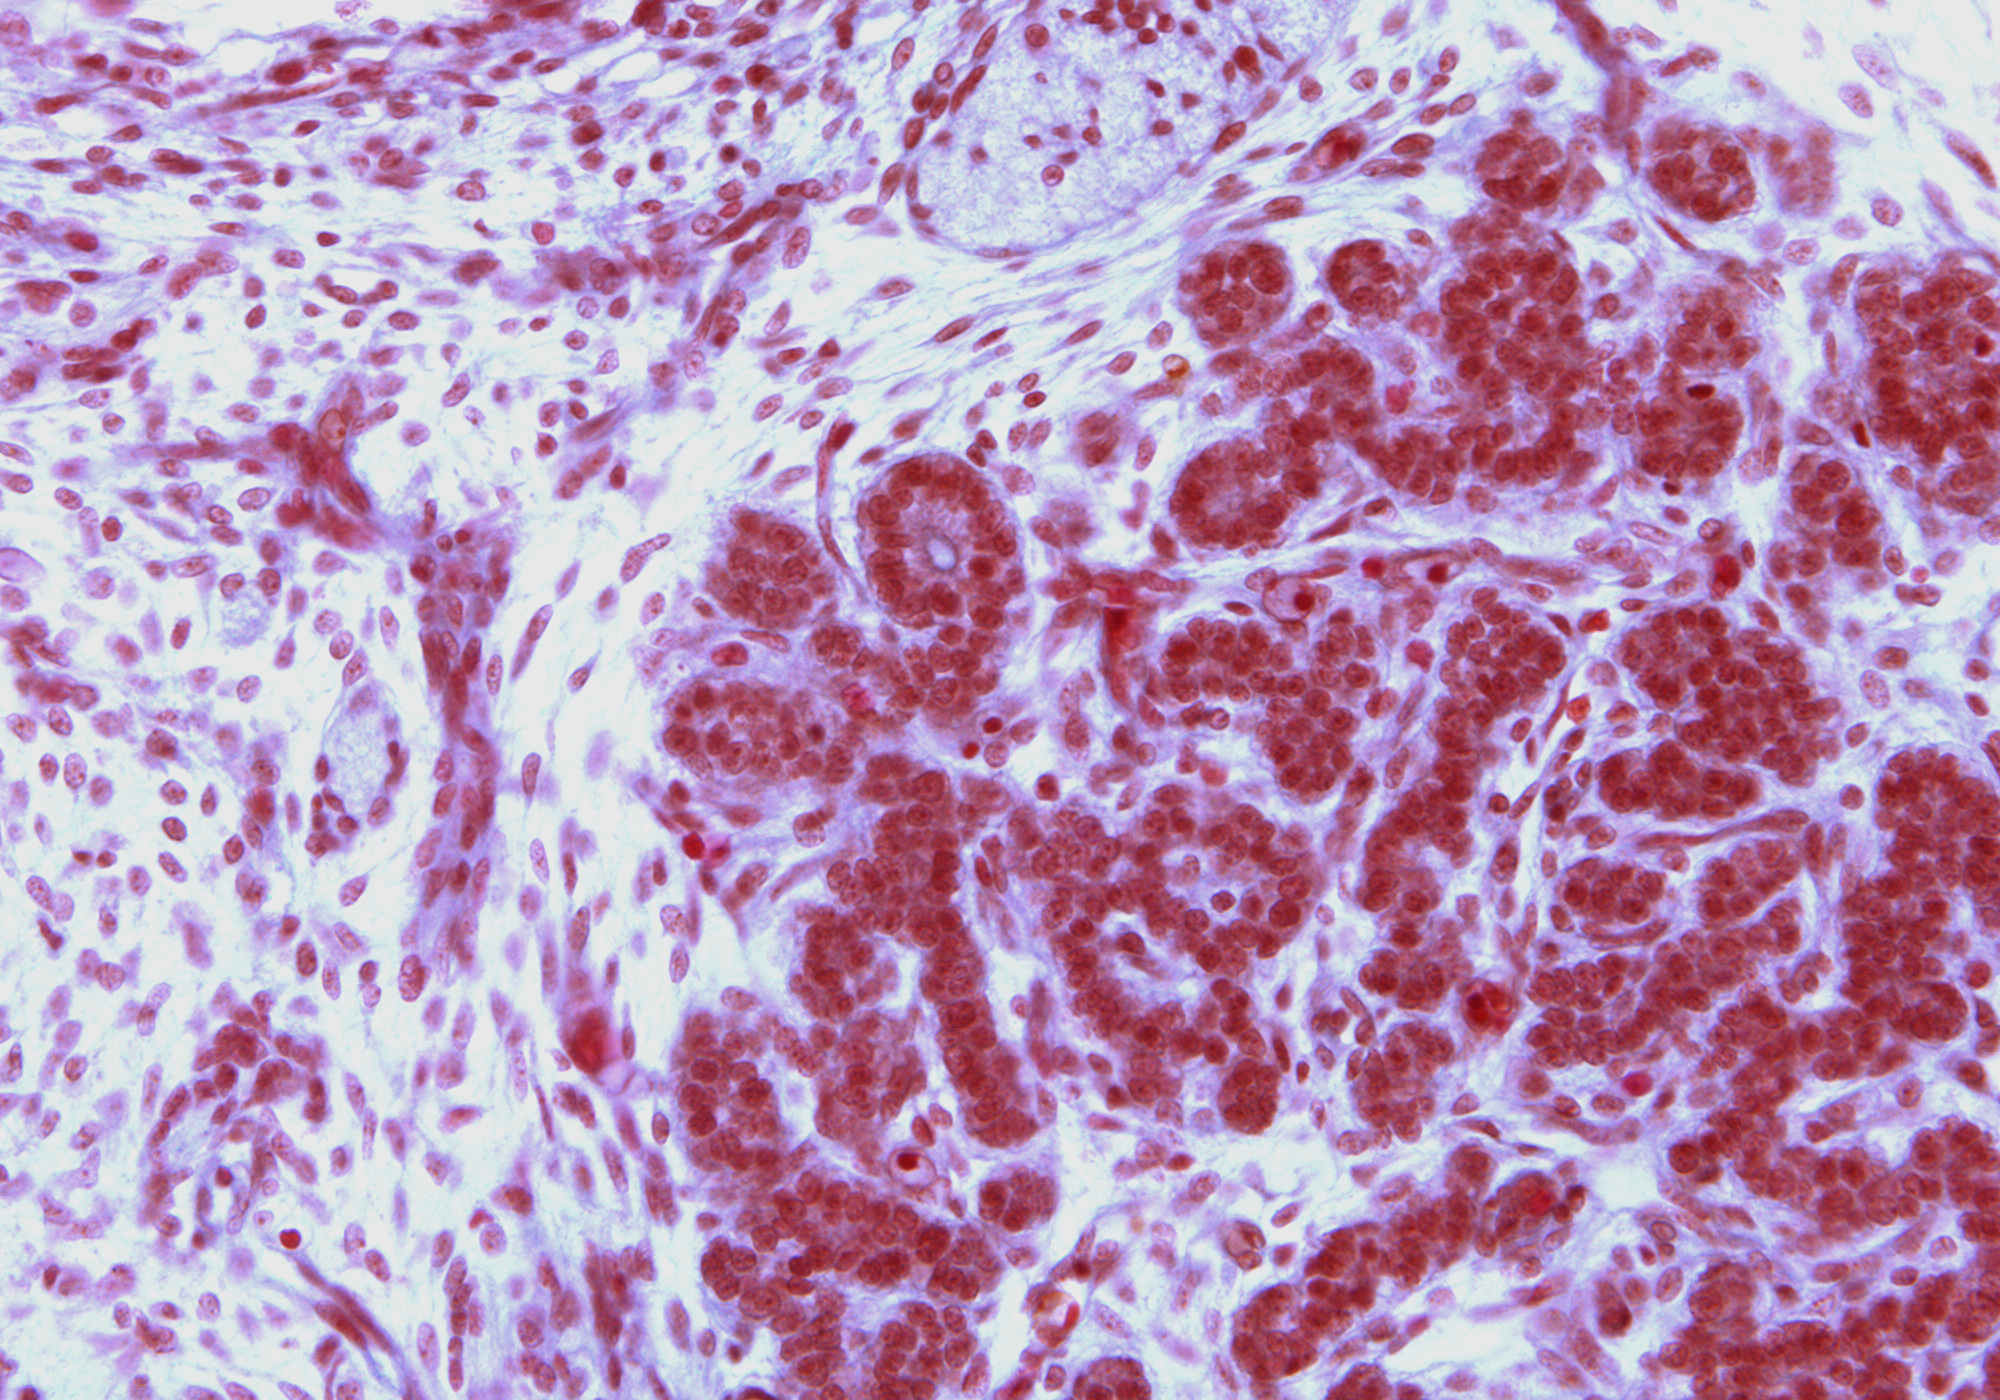

Tissue

–

Thyroid Gland

Carnegie Embryo #9226

Location:

85-01-01